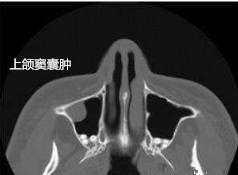

1.鼻窦浆液性囊肿多见于上额窦,蝶窦相对少见,与变态反应或鼻慢性炎症有关。由于窦腔粘膜浆液腺导管阻塞,分泌物蓄积,腺体膨胀,小潴留嚢肿破裂并融合,形成较大囊肿。并且,导管上皮保持完整继续分泌,使窦腔黏膜从骨壁突出,直到一个大囊肿形成。囊肿通常不膨胀性生长,也不侵蚀骨质。CT可见紧贴窦壁的半圆形或类圆形软组织密度或水样密度影,囊肿突入窦腔,边缘光滑清晰,无骨质破坏。一般多无症状,经常体检时做头颅MR或CT偶然发现,可以采取保守观察的方法,不需手术及药物治疗。极少数会自行破溃,从鼻腔内流出淡黄色清亮液体。